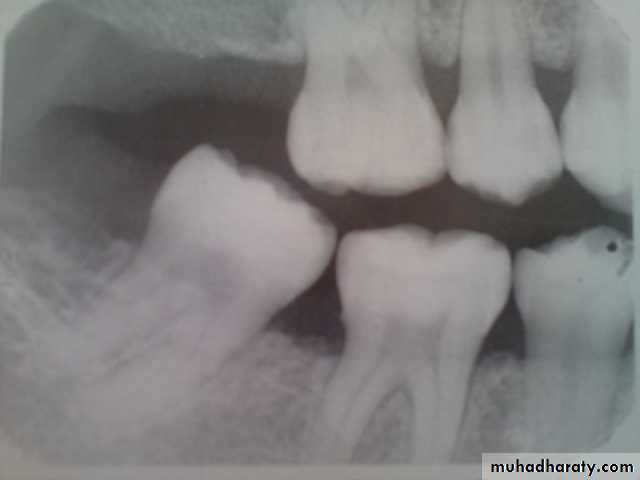

vertical (angular) bone loss:

Bone loss doesn’t occur in plane parallel to CEJs of adjacent teeth.Vertical bone loss

Vertical bone defects-are also called proximal intrabony defects. The defect extends apically2- Distribution